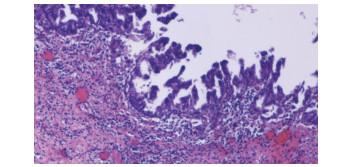

Intraductal papillary neoplasm of the bile duct with atrophy of the hepatic left lateral lobe: A case report